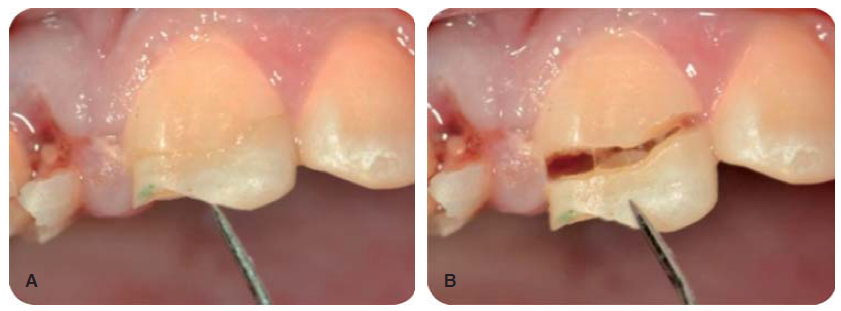

Debido a la evolución de dos días desde el accidente, el paciente presenta dolor e inflamación a la exploración extraoral, durante la exploración intraoral se observa la exposición pulpar de los dientes involucrados (Figura 2) e indica el tratamiento de urgencia a seguir, para disminuir el dolor e inflamación.

Consistió en el retiro de los fragmentos dentales (Figuras 3 a 6) (4,5) para tener una mejor visión del área y del posible tratamiento a ejecutar. Se realizó bajo anestesia local con lidocaína al 2% con epinefrina 1:100,000, luego se realizó la pulpectomía de los dientes 12, 11 y 21 dejando una medicación de hidróxido de calcio al 35% (UtraCal ® XS, pH 12.5, Ultradent) y como curación temporal un ionómero de vidrio (Figura 7).11,12

Paciente de sonrisa gingival que presenta fractura complicada de corona del diente 21 en el tercio medio coronal (Figura 3) y del diente 12 en el tercio cervical (Figura 4), fractura complicada de corona y raíz del diente 11 (Figura 5); gingivitis inducida por placa dentobacteriana (Figura 7), trasposición de los dientes 13 y 14, anodoncia verdadera de los dientes 15, 35 y 45, presentando los dientes temporales 55, 75 y 85.